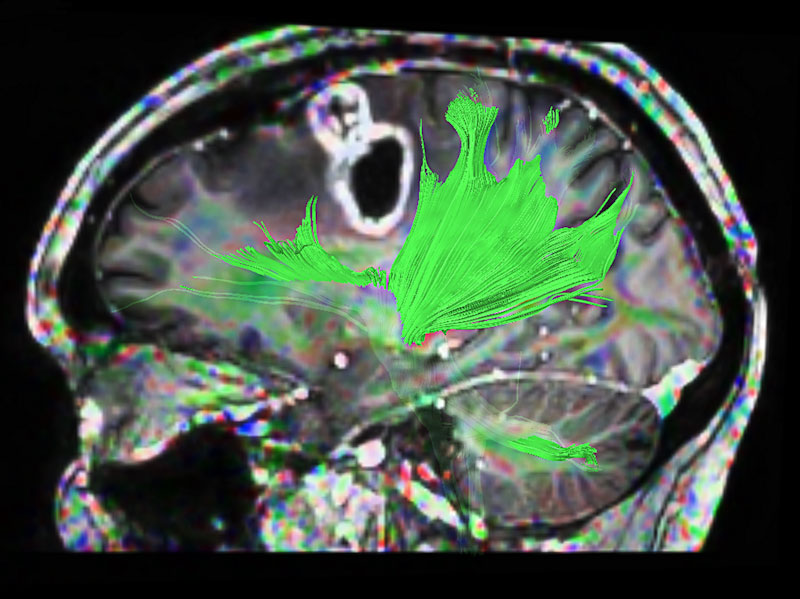

Axial DTI (FiberTrak)